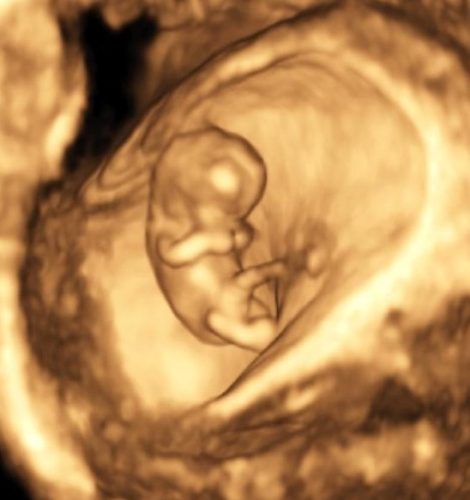

Échographie 3D de datation © D.R.

En échographie, la plus fréquente est sans doute la grossesse arrêtée. C’est un moment cruel pour une femme : elle arrive pleine d’espoir et on découvre ensemble que sa grossesse n’évolue pas. Et puis il y a les anomalies fœtales, les trisomies, les malformations cardiaques, les fentes labiales, beaucoup de choses différentes et de gravité très variable. L’échographie dite de datation est la plus précoce, facultative mais fréquente car bien utile pour localiser la grossesse et compter le nombre d’embryons. L’échographie du premier trimestre est essentielle pour dater la grossesse par la mesure de longueur cranio-caudale (LCC), mesurer la clarté nucale (CN) et faire une première analyse morphologique. Le dépistage de la trisomie par marqueurs sériques est proposé mais non imposé.